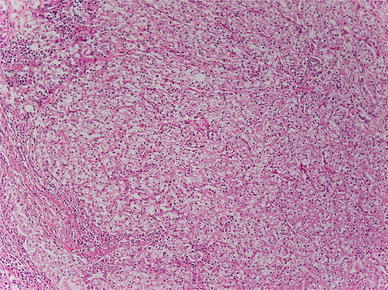

Histopathological findings: small alveolar proliferations of atypical cells with clear cytoplasm were noted (Fig. 4). The diagnosis was clear cell carcinoma. Because histopathological examination at the time of right nephrectomy in 2002 also revealed proliferation of tumor cells with clear cytoplasm (Fig. 5), metastasis of renal cancer to the esophagus was suggested.

Fig. 5.

Histopathological findings: substantial proliferation of tumor cells with clear cytoplasm